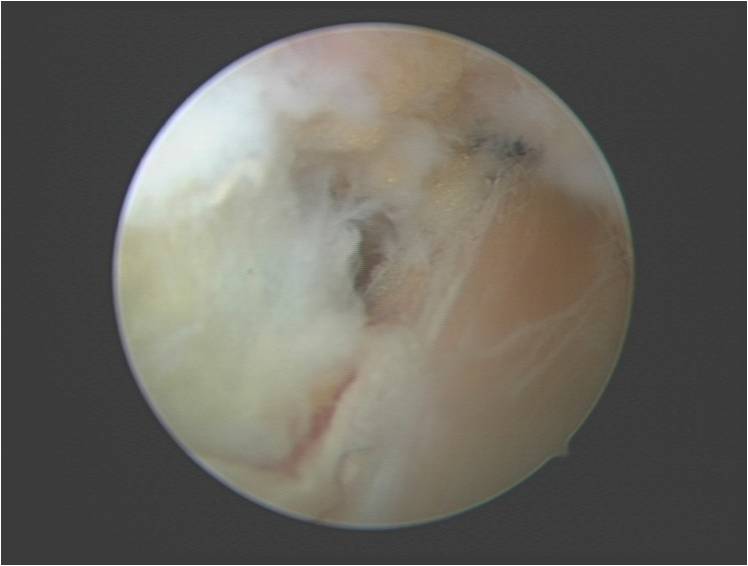

肩关节镜手术